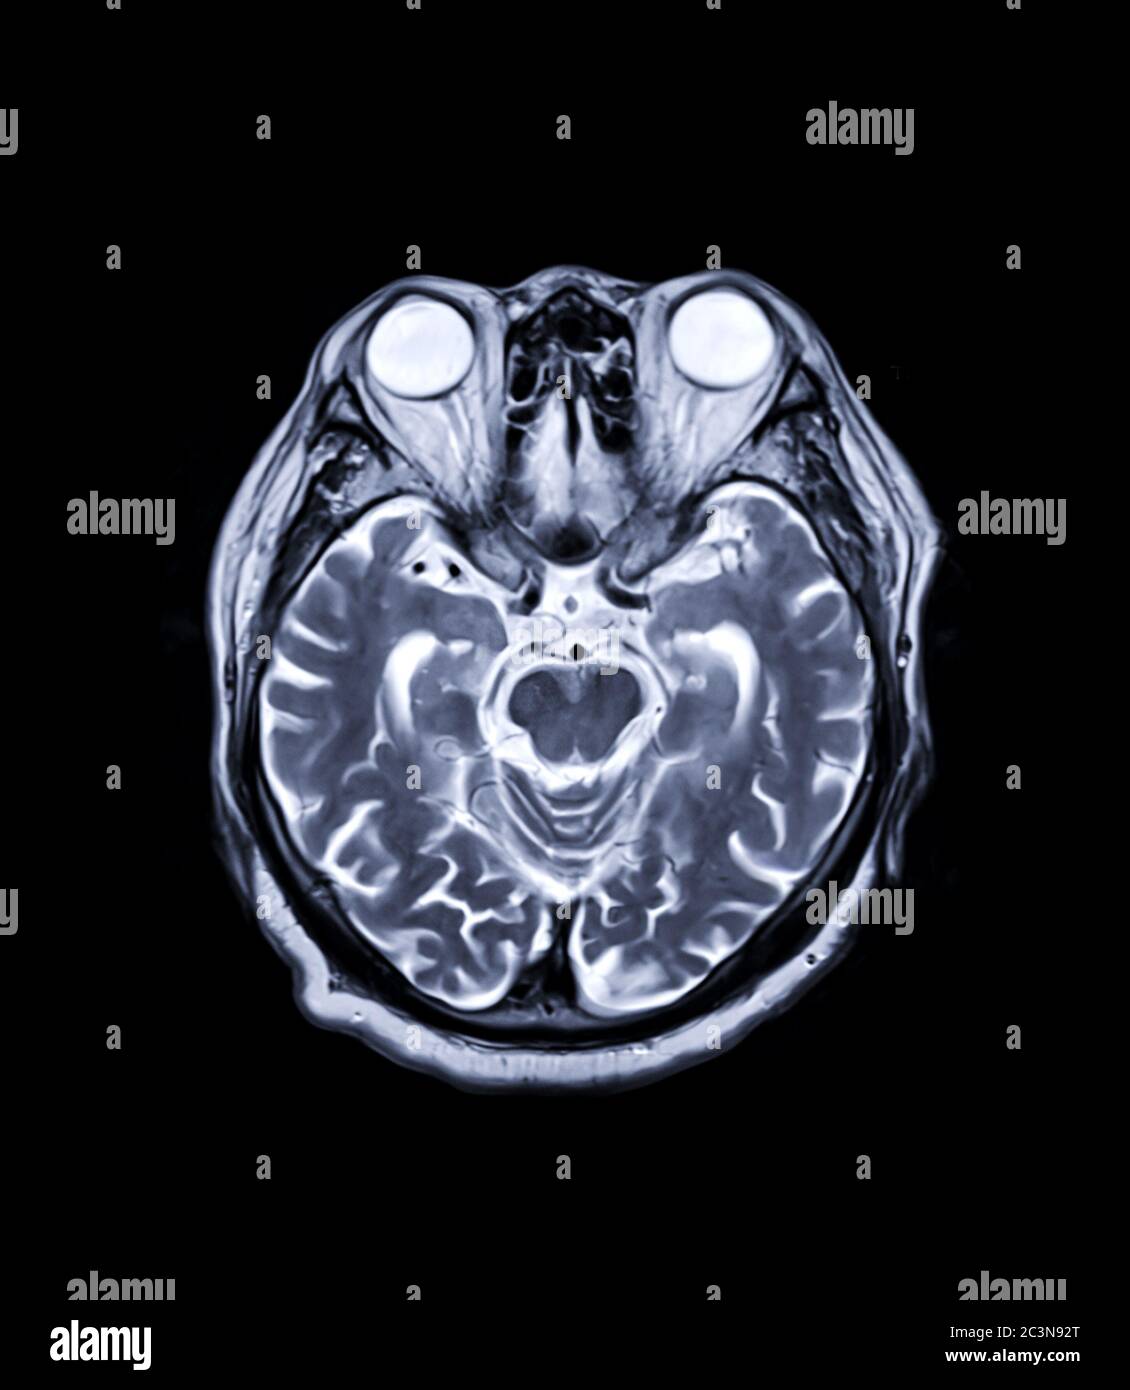

MRI brain axial and sagittal plane with gadolinium contrast for detect

MRI brain Axial T2 technique for detect a variety of conditions of the What Can Mri Brain Detect This information can help guide. A head mri is a useful tool for detecting a number of brain conditions, including: Aneurysms, or bulging in the blood vessels of the brain. Functional mri can be used to examine the brain's anatomy and show which parts of the brain are handling critical functions, language and movements. Mri can detect abnormalities that might. What Can Mri Brain Detect.